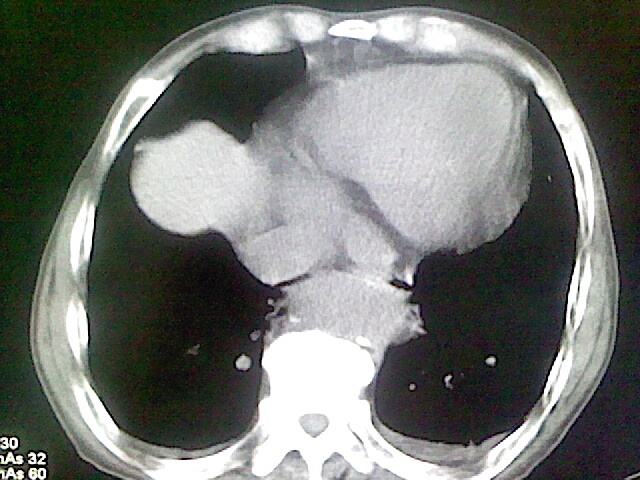

以下是引用zsl6918在2008-8-28 16:49:00的发言:[br]双肺炎性病灶,食管狭窄估计与心房增大压迫所致。

以下是引用xulianj在2008-8-28 20:36:00的发言:[br]慢支肺气肿伴感染,右上肺陈旧性结核;食道建议胃镜检查。

以下是引用wqs571018在2008-8-28 21:18:00的发言:[br]慢支继发感染,右上肺陈旧性结核;食道建议胃镜检查。